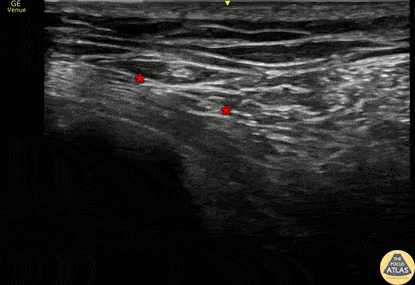

50s M presented with side pain after a fall, and on imaging was found to have multiple unilateral rib fractures without other injuries. In order to help with pain control, a serratus anterior plane block was performed. The block is shown here, with the needle entering from the posterior/lateral aspect and placing anesthetic in the fascial plane (*) superficial to the serratus anterior muscle and deep to the latissimus dorsi muscle. This patient had improvement in his pain and was able to be discharged. Dr. Riku Moriguchi, PGY3 and Dr. Smitha Bhaumik, PGY4 Denver Health Residency in Emergency Medicine